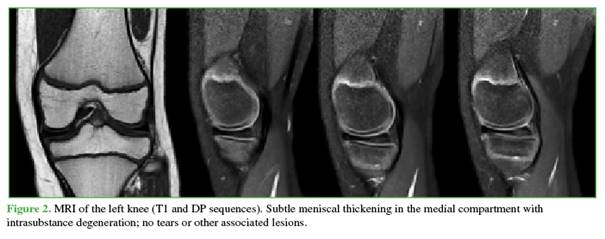

A 14-year-old male, with asthma and active in sports, presented to the Emergency Department with a two-week history of left knee pain sustained during soccer training. He had persistent pain associated with limping and intermittent locking. After initial evaluation and radiographs (Figure 1), outpatient management was chosen under the suspicion of a sprain. Symptoms decreased slightly, and locking ceased.

He was referred to an orthopedic subspecialist. Physical examination revealed tenderness on palpation of the medial joint line, painful flexion-extension with full range of motion (0-130°), and a positive medial McMurray test; the remainder of the exam was normal. Given these findings, an MRI of the left knee was requested (Figure 2). Imaging showed an enlarged medial meniscus (incomplete) without displacement, with intrameniscal degeneration.